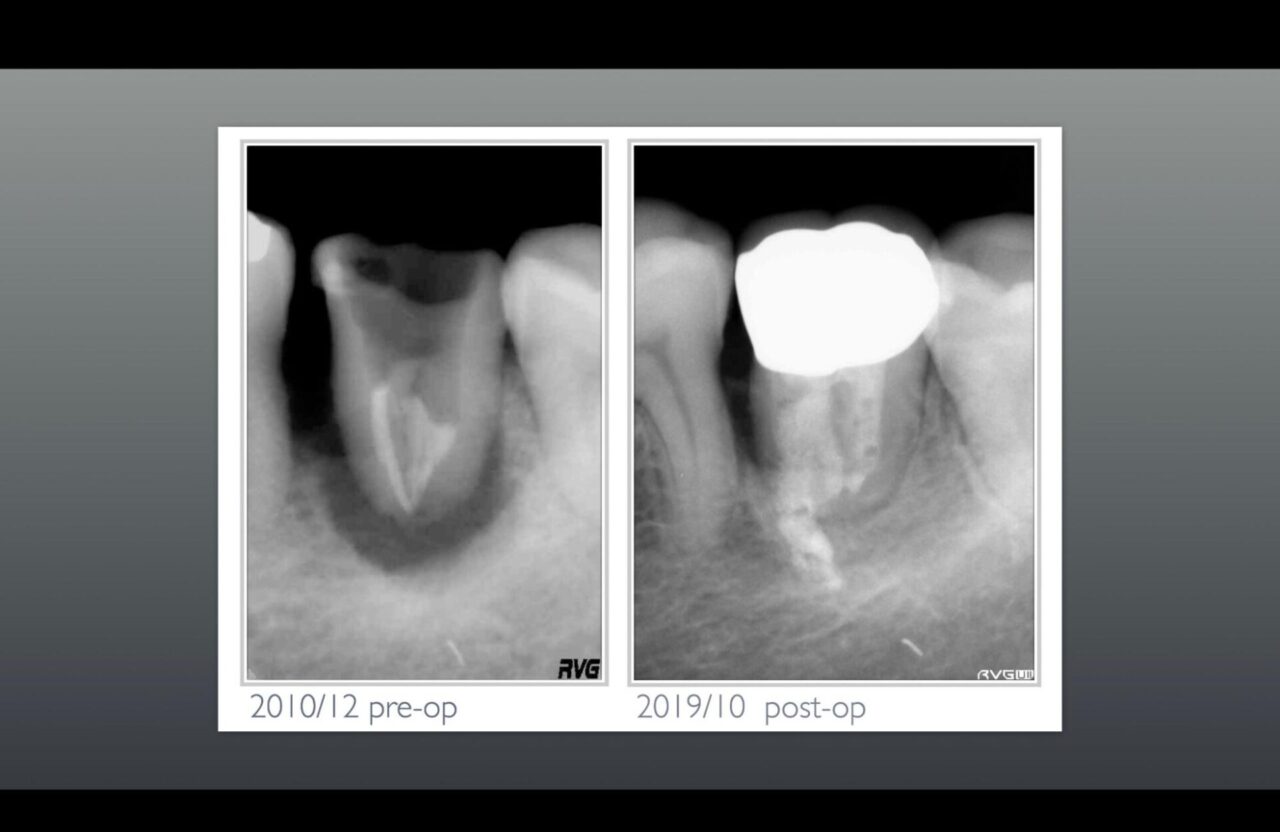

術前のレントゲンと術後のレントゲン①

術前のレントゲンを診ると歯根破折を疑われるレントゲン像を示しており、標準的な診断では抜歯になる症例です。アメリカ帰りには絶対に治せない症例です。

この歯の治療は、最初1回法で根管充填、ファイバーポストまで1日で行ったが頬からのサイナストラクト、フィステルが消失しないため、6ヶ月後に近心根のみもう一度根管治療を行った。頬側からの掻爬や、物理的、化学的洗浄を十分に行いバイオセラミックで根管充填をした症例です。